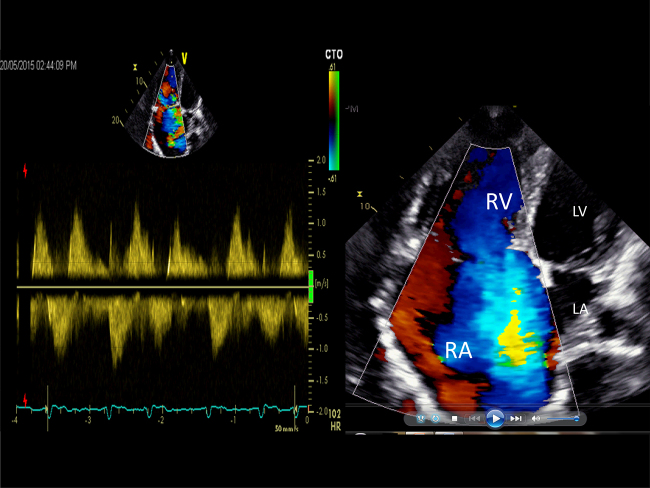

Fig. 3.

The left panel shows to-and-fro flow across the tricuspid orifice with a peak velocity of approximately 100 cm/s. The right panel shows severe low pressure (laminar) tricuspid regurgitation in apical 4-chamber view.